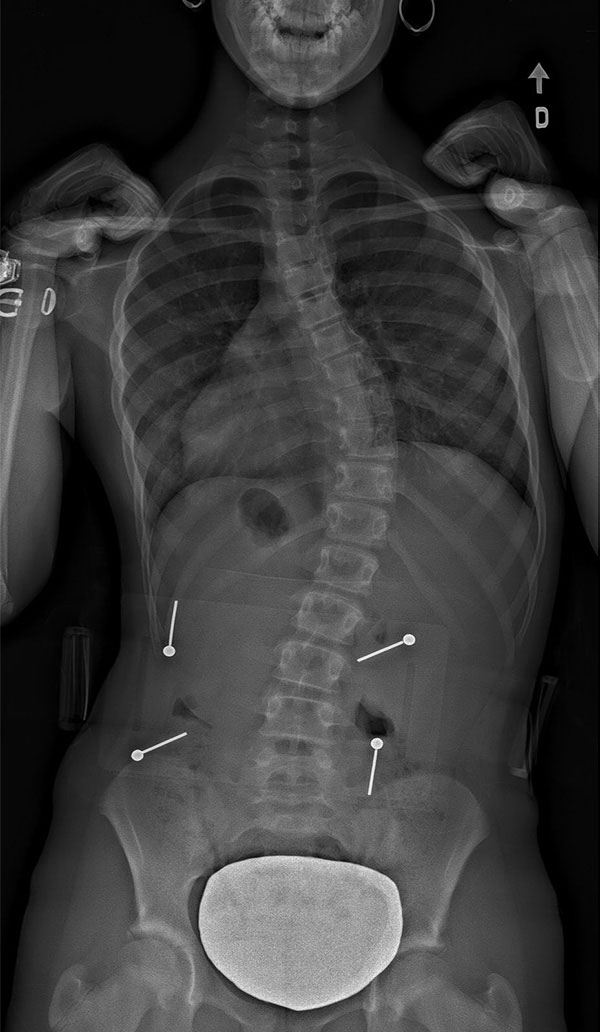

Souvent perçue comme une déformation en « S » ou un escalier en colimaçon, la scoliose est en fait une véritable déformation en 3 dimensions de la colonne vertébrale en torsion. Celle-ci implique une courbure latérale de plus de 10° ainsi qu'une rotation anormale des vertèbres.

La Scoliose thoracique (dorsale) est située dans la région de la colonne vertébrale où se trouvent les côtes.